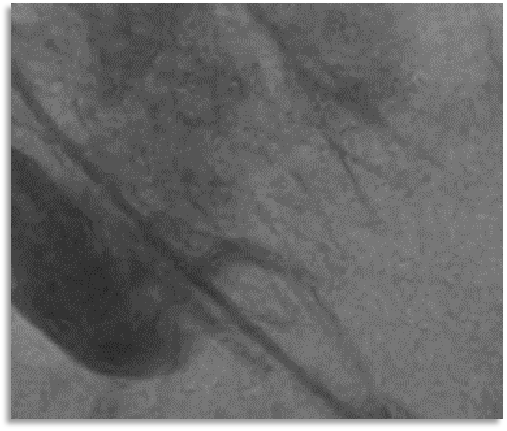

球囊预扩张

10mm*10cm小球囊预扩

23mm Z-Med预扩张

根据预扩表现决定使用26mm瓣膜